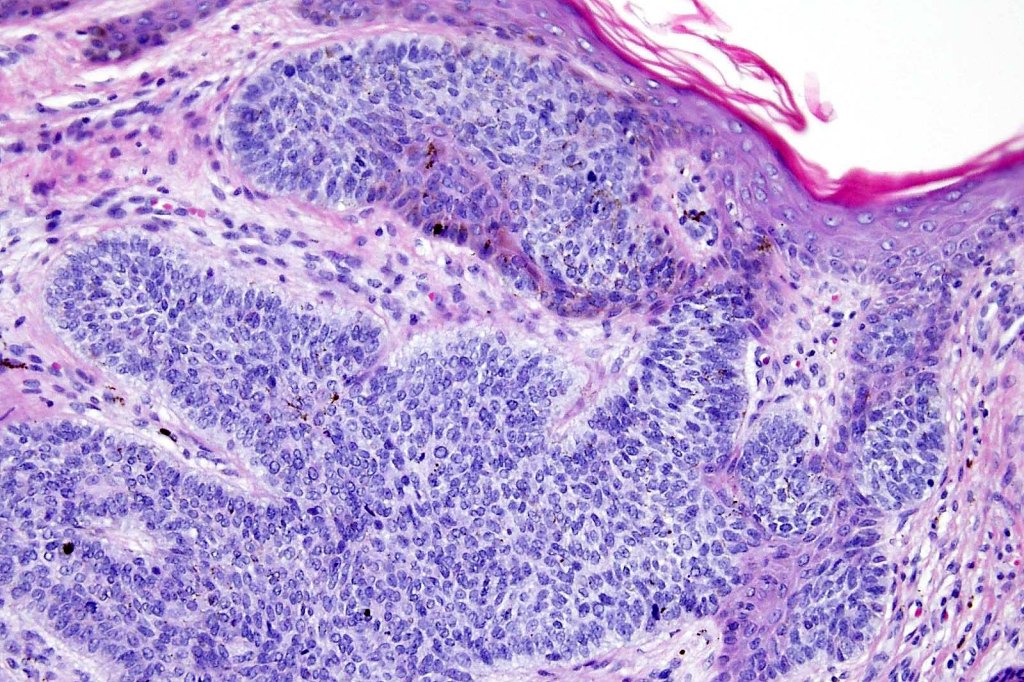

•Anastomosing basaloid, narrow epithelial strands associated with a prominent fibrous (sometimes myxoid) stroma

•Peripheral palisade

•Round to oval vesicular nuclei with small nucleoli

•Mitoses very scanty or absent

•Hair germs sometimes present